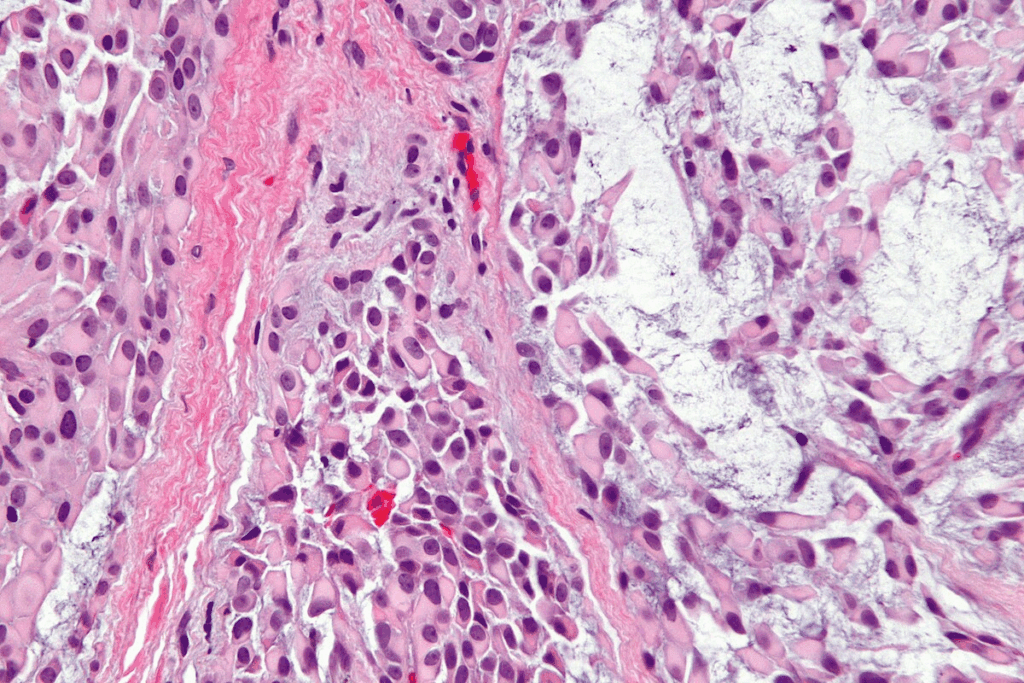

Cellular Structure and Abnormalities

Neoplastic cells look different under a microscope. They can be bigger, smaller, or shaped differently. These changes help doctors spot tumors.

- Anaplasia: Cells lose their normal shape, looking like young cells.

- Pleomorphism: Cells vary in size and shape, showing a loss of normal structure.

- Hyperchromasia: Nuclei are darker because they have too much DNA.

Biopsy and Histopathological Analysis

The final diagnosis often comes from a biopsy and histopathological analysis. A biopsy takes a tissue sample from the suspected tumor. A pathologist then examines it under a microscope.

The histopathological analysis gives important info about:

- Tumor type

- Grade of malignancy

- Presence of genetic mutations